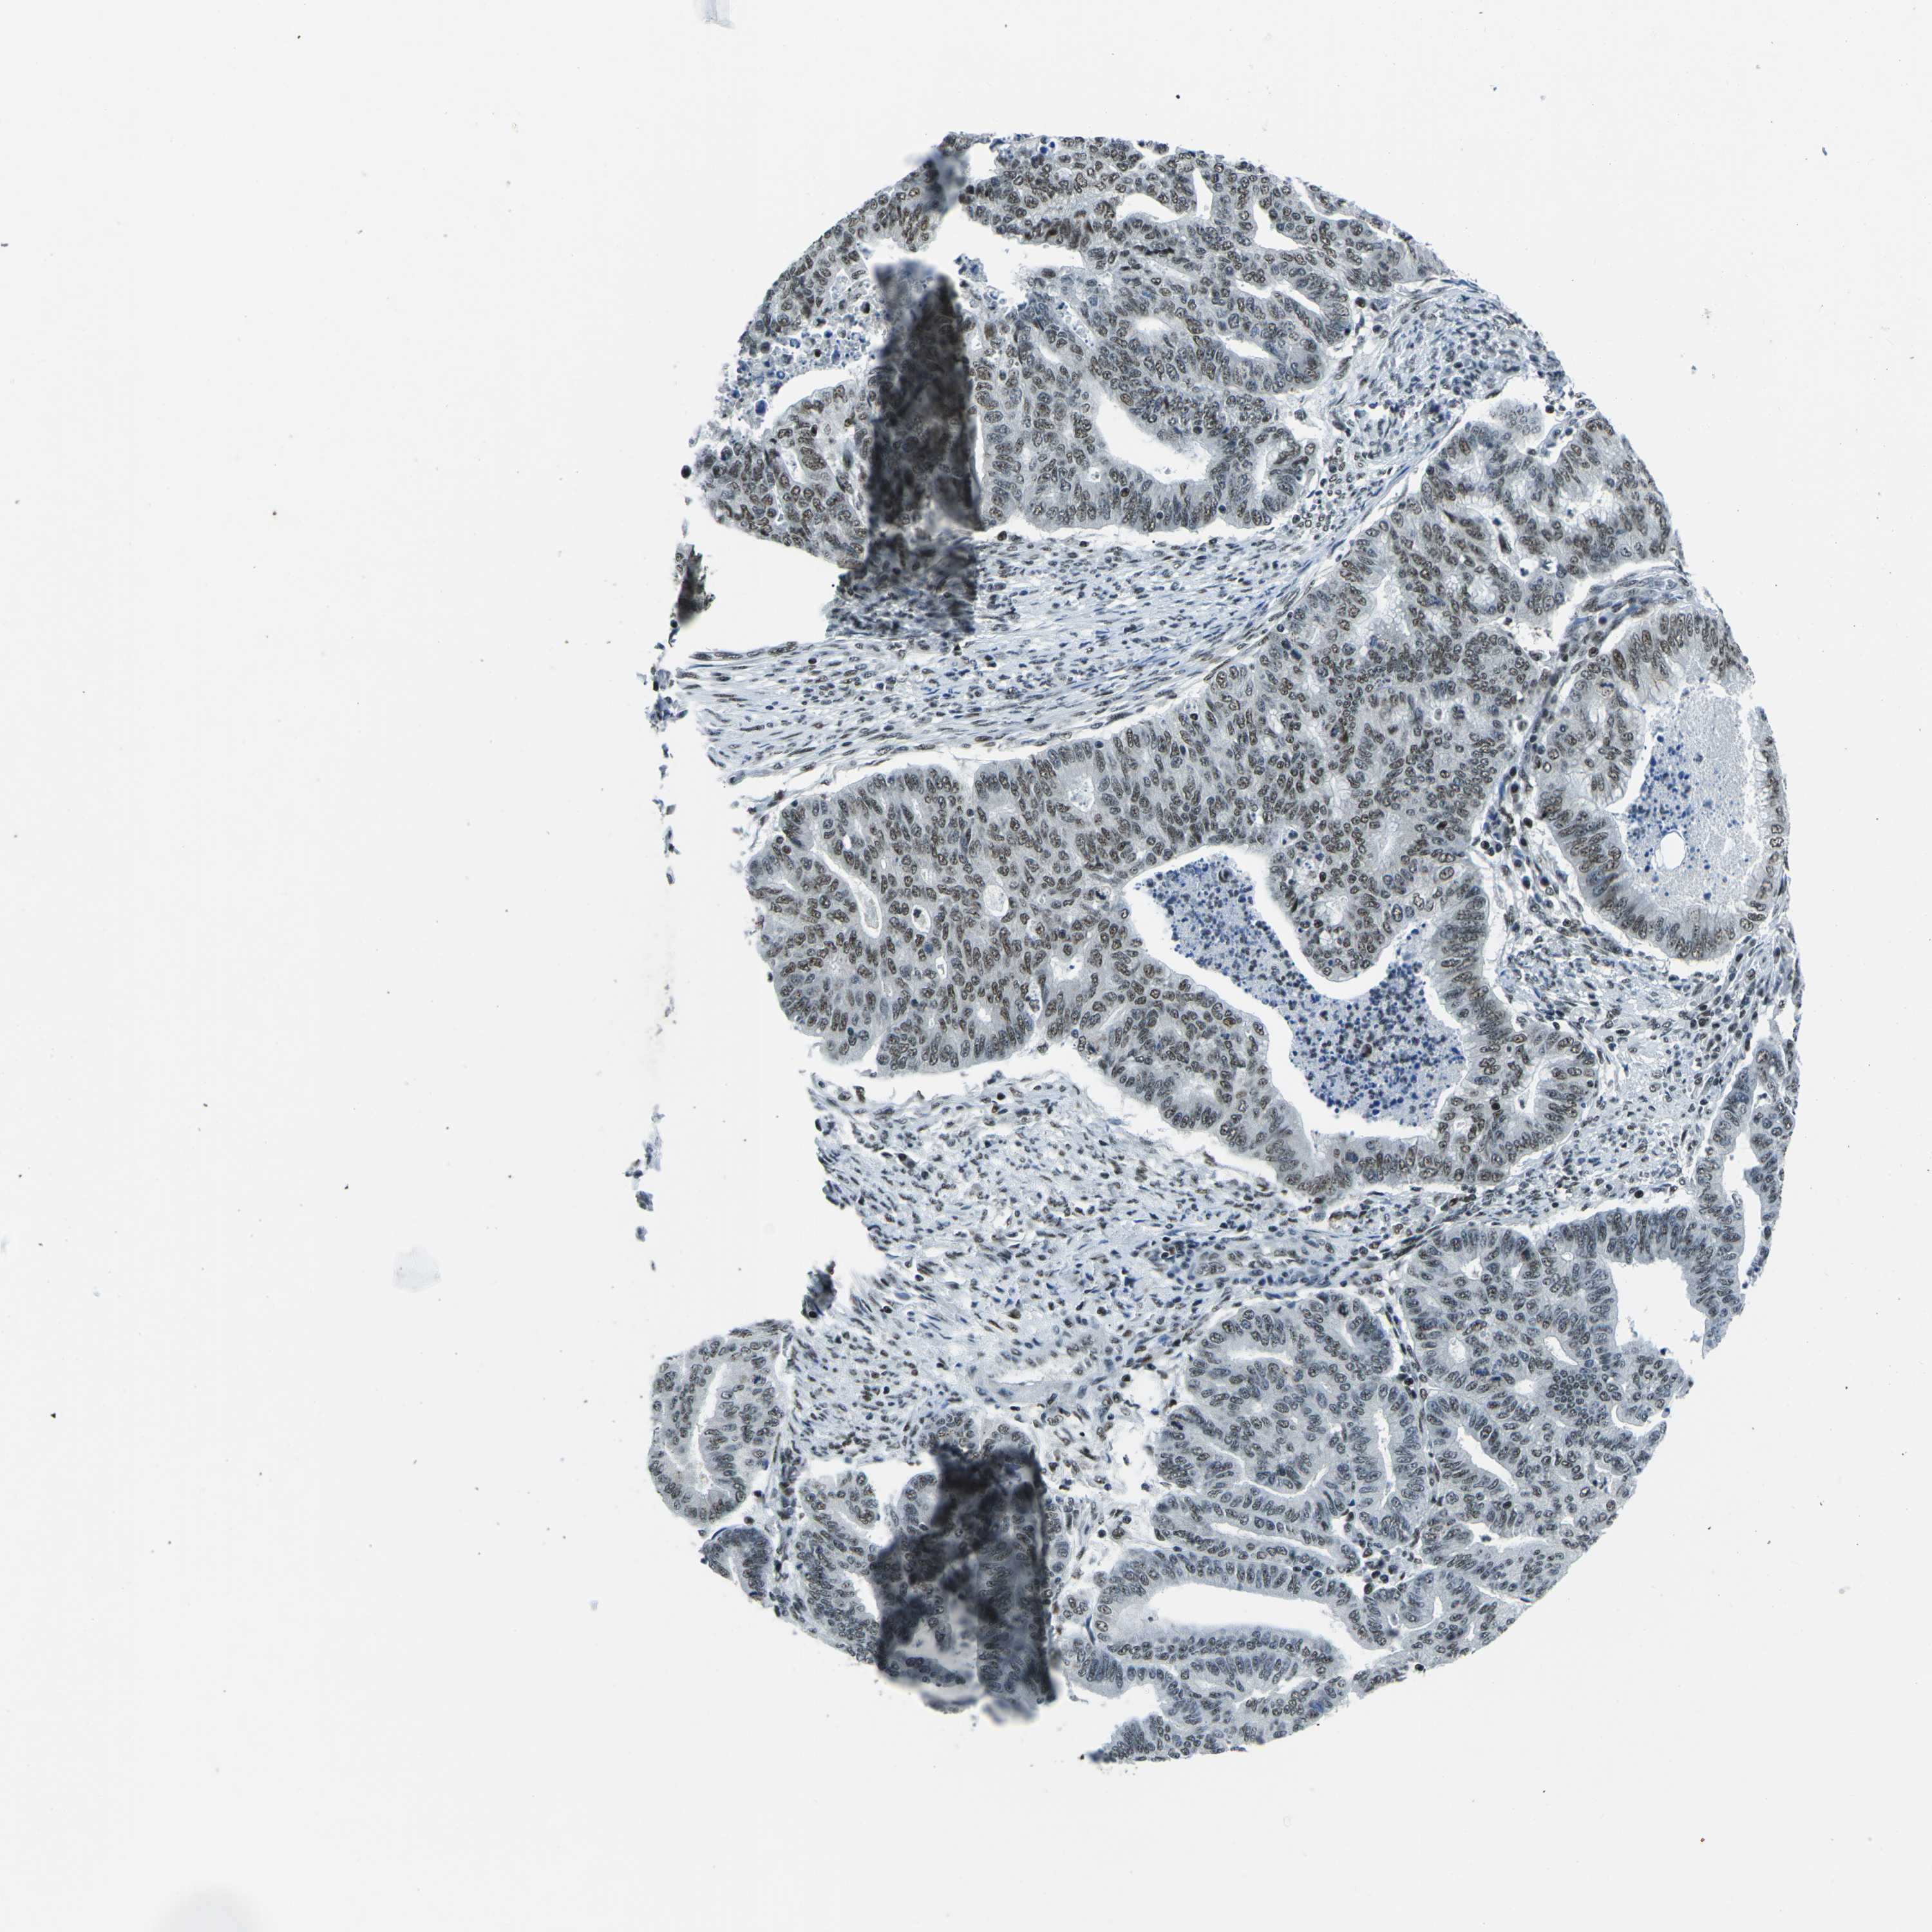

ENDOMETRIAL CANCER - Protein expressioni

A mouse-over function shows sample information and annotation data. Click on an image to view it in a full screen mode. Samples can be filtered based on level of antibody staining by selecting one or several of the following categories: high, medium, low and not detected. The assay and annotation is described here.

Note that samples used for immunohistochemistry by the Human Protein Atlas do not correspond to samples in the TCGA dataset.

Antibody stainingi

Antibody staining in the annotated cell types in the current human tissue is reported as not detected, low, medium, or high, based on conventional immunohistochemistry profiling in selected tissues. This score is based on the combination of the staining intensity and fraction of stained cells.

Each image is clickable and will lead to virtual microscopy that enables deeper exploration of all samples and also displays staining intensity scores, fraction scores and subcellular localization as well as patient and tissue information for each sample.

Antibody HPA019703

Antibody CAB016547

Staining

High

Medium

Low

Not detected

Intensity

Strong

Moderate

Weak

Negative

Quantity

>75%

75%-25%

<25%

None

Location

Nuclear

Cytoplasmic/membranous

Cytoplasmic/membranous,nuclear

Adenocarcinoma, NOS

Adenoma, NOS